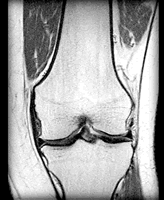

与非类固醇类抗炎药(NSAID)相比,曲马朵不影响关节软骨,也不会导致胃肠道出血及肾脏问题,因此在骨性关节炎治疗中的应用日渐增多。为评价口服曲马朵的止痛效果及对关节功能的影响,美国学者Cepeda等检索了Cochrane对照临床试验注册数据库、 Medline、Embase和Lilacs等数据库截至2005年8月的资料,对其中的相关研究进行了分析。分析结果于2006年7月19日在线发表。(Cochrane Database Syst Rev 2006, 3: CD005522)

共11项随机对照研究纳入分析,包括接受曲马朵或联用曲马朵和乙酰氨基酚治疗的1019例患者(治疗时间为1周至3个月)和接受安慰剂或NSAID等活性对照药物治疗的920例患者。结果显示,接受曲马朵治疗者的疼痛得分比安慰剂组低8.5分(100分制),相当于其疼痛强度比基线时减轻了12%,认为病情(关节僵硬及疼痛)得到中度改善的患者比安慰剂组多37%。但曲马朵所致主要不良事件和次要不良事件的发生危险分别为安慰剂组的2.6倍和2.27倍。每8例接受曲马朵或联用曲马朵和对乙酰氨基酚治疗的患者中,就有1例因不良事件而停药。由于资料有限,曲马朵与其他活性药物在疗效及副作用方面的比较还不得而知。

评价者结论:曲马朵或联用曲马朵和对乙酰氨基酚可减轻骨性关节炎患者的疼痛,缓解其症状,并改善其关节功能。曲马朵的副作用(如恶心、呕吐、眩晕、便秘、疲劳、头痛等)虽为不危及生命的可逆性反应,但可导致相当数量的患者停药,从而限制了其在骨性关节炎治疗中的应用。, 百拇医药